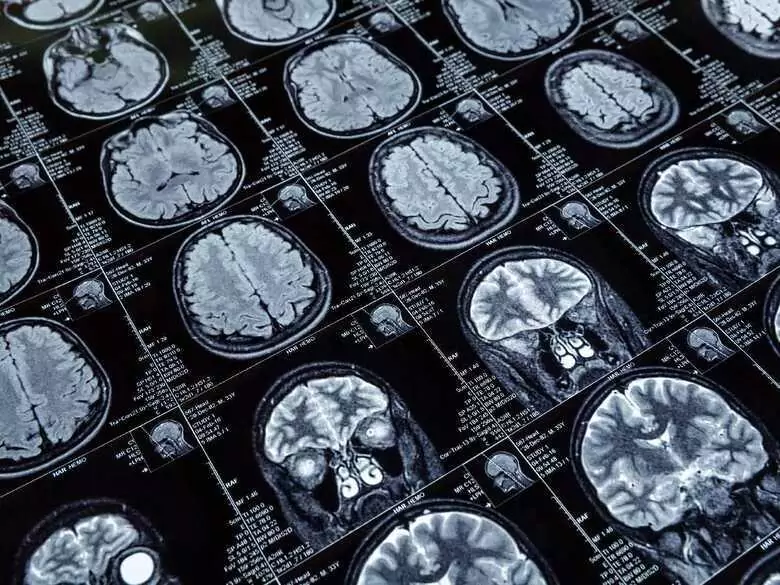

L'accident vasculaire cérébral peut entraîner un certain nombre de séquelles. Celles-ci ne doivent jamais être sous-estimées. Dans la plupart des cas, elles ont un impact significatif sur la capacité du patient à fonctionner de manière efficace et indépendante. Ces séquelles dépendent de l'état de santé du patient avant l'AVC ainsi que de la topographie et de la taille du foyer ischémique.